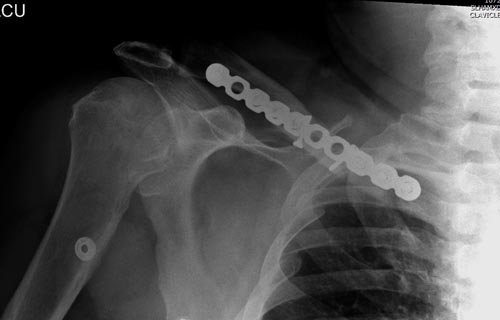

В заключение, только 25% изолированных переломов ключицы, леченных консервативным методом не срастаются, а из них 1/3 симптоматические. Болезненные ложные суставы надо оперировать, и здесь представлен случай свежего болезненного ложного сустава, оперированного через 4 месяца.

Освобожден средний фрагмент и боковая компрессия лагированием, фиксация пластиной..